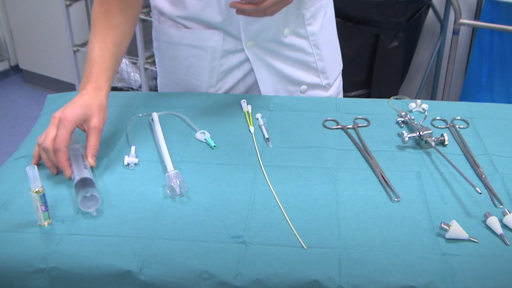

リピオドール®を使用した子宮卵管造影(HSG)の準備

リピオドール®を使用した子宮卵管造影(HSG)の手順